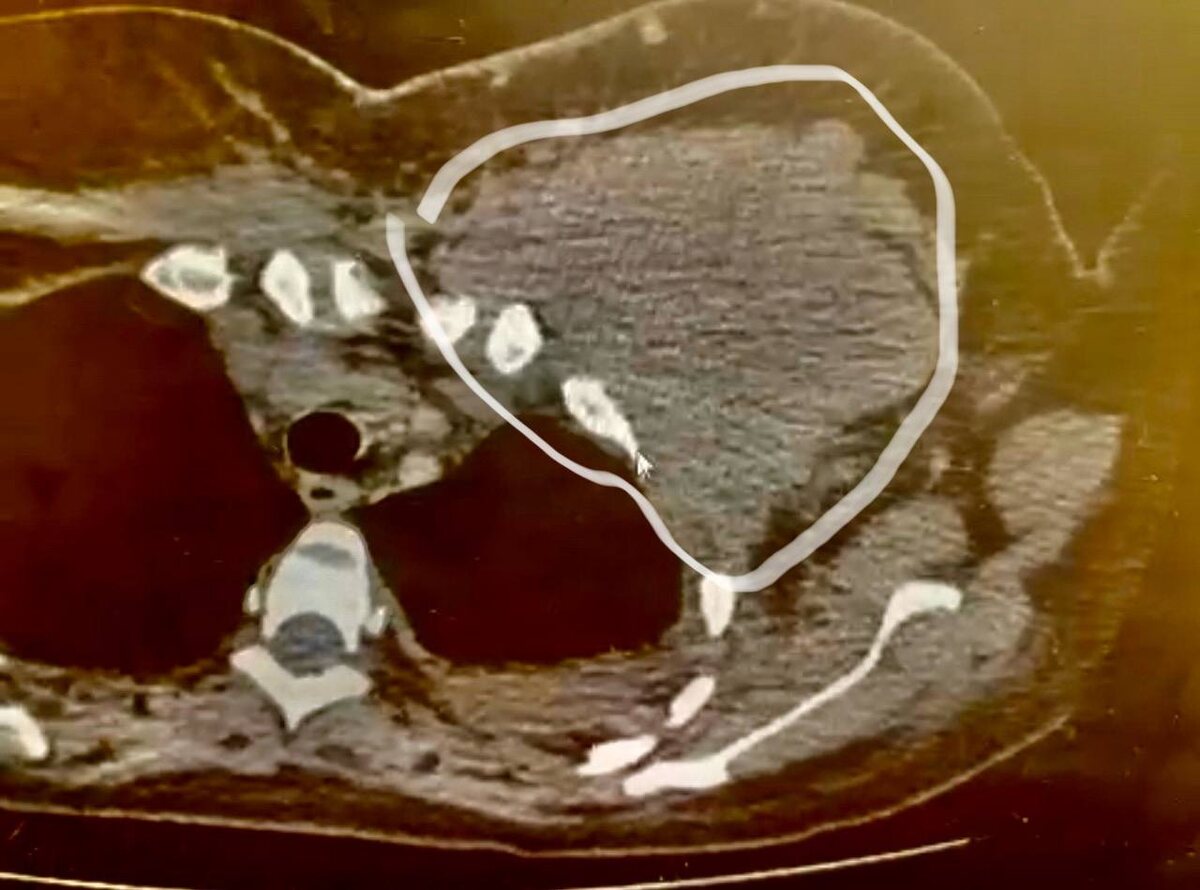

Опухоль молочной железы, проростающая в грудную клетку со здавлением легкого. (фото из личных архивов)